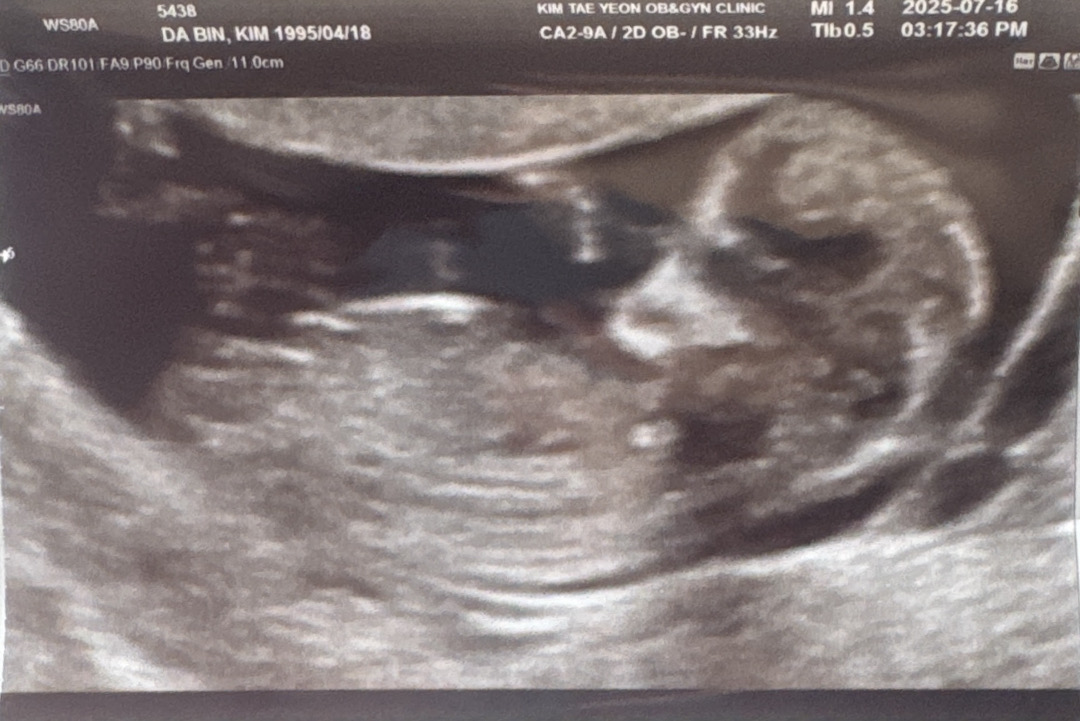

아들일까요 딸일까요 👏🏻👏🏻

니프티로 7월 말에 결과 나오는데 잘 보시는 분들 계신가여 ㅎㅎ.. ㅎㅎ

각도상 딸같아용